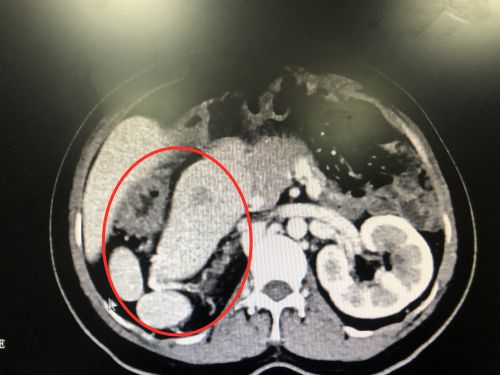

ct显示患者有多个脾脏。(红圈内)

入院后的CT检查发现,张女士不仅有“肝胆管结石并胆管炎”,而且脾脏分裂成4个;不仅如此,4个脾脏和胃、十二指肠都长反了位置——本应在腹腔左侧的脾脏和胃跑到右边,而原本应该在右侧的十二指肠则跑到了左边。

考虑到患者曾做过多次腹部手术且手术耗时长,预计腹腔粘连及炎症都比较严重;加之患者多脏器反位,解剖位置难以判断,令本就困难的手术难上加难。

“多脾综合征合并多脏器反位,还患有复杂的肝胆管结石,手术能够如此成功,国内外文献都没有类似报道”,成伟主任医师表示,此例手术的成功标志着捷克论坛 肝胆胰脾外科在多脾综合征、多脏器反位合并复杂肝胆管结石的手术治疗方面居世界领先水平。